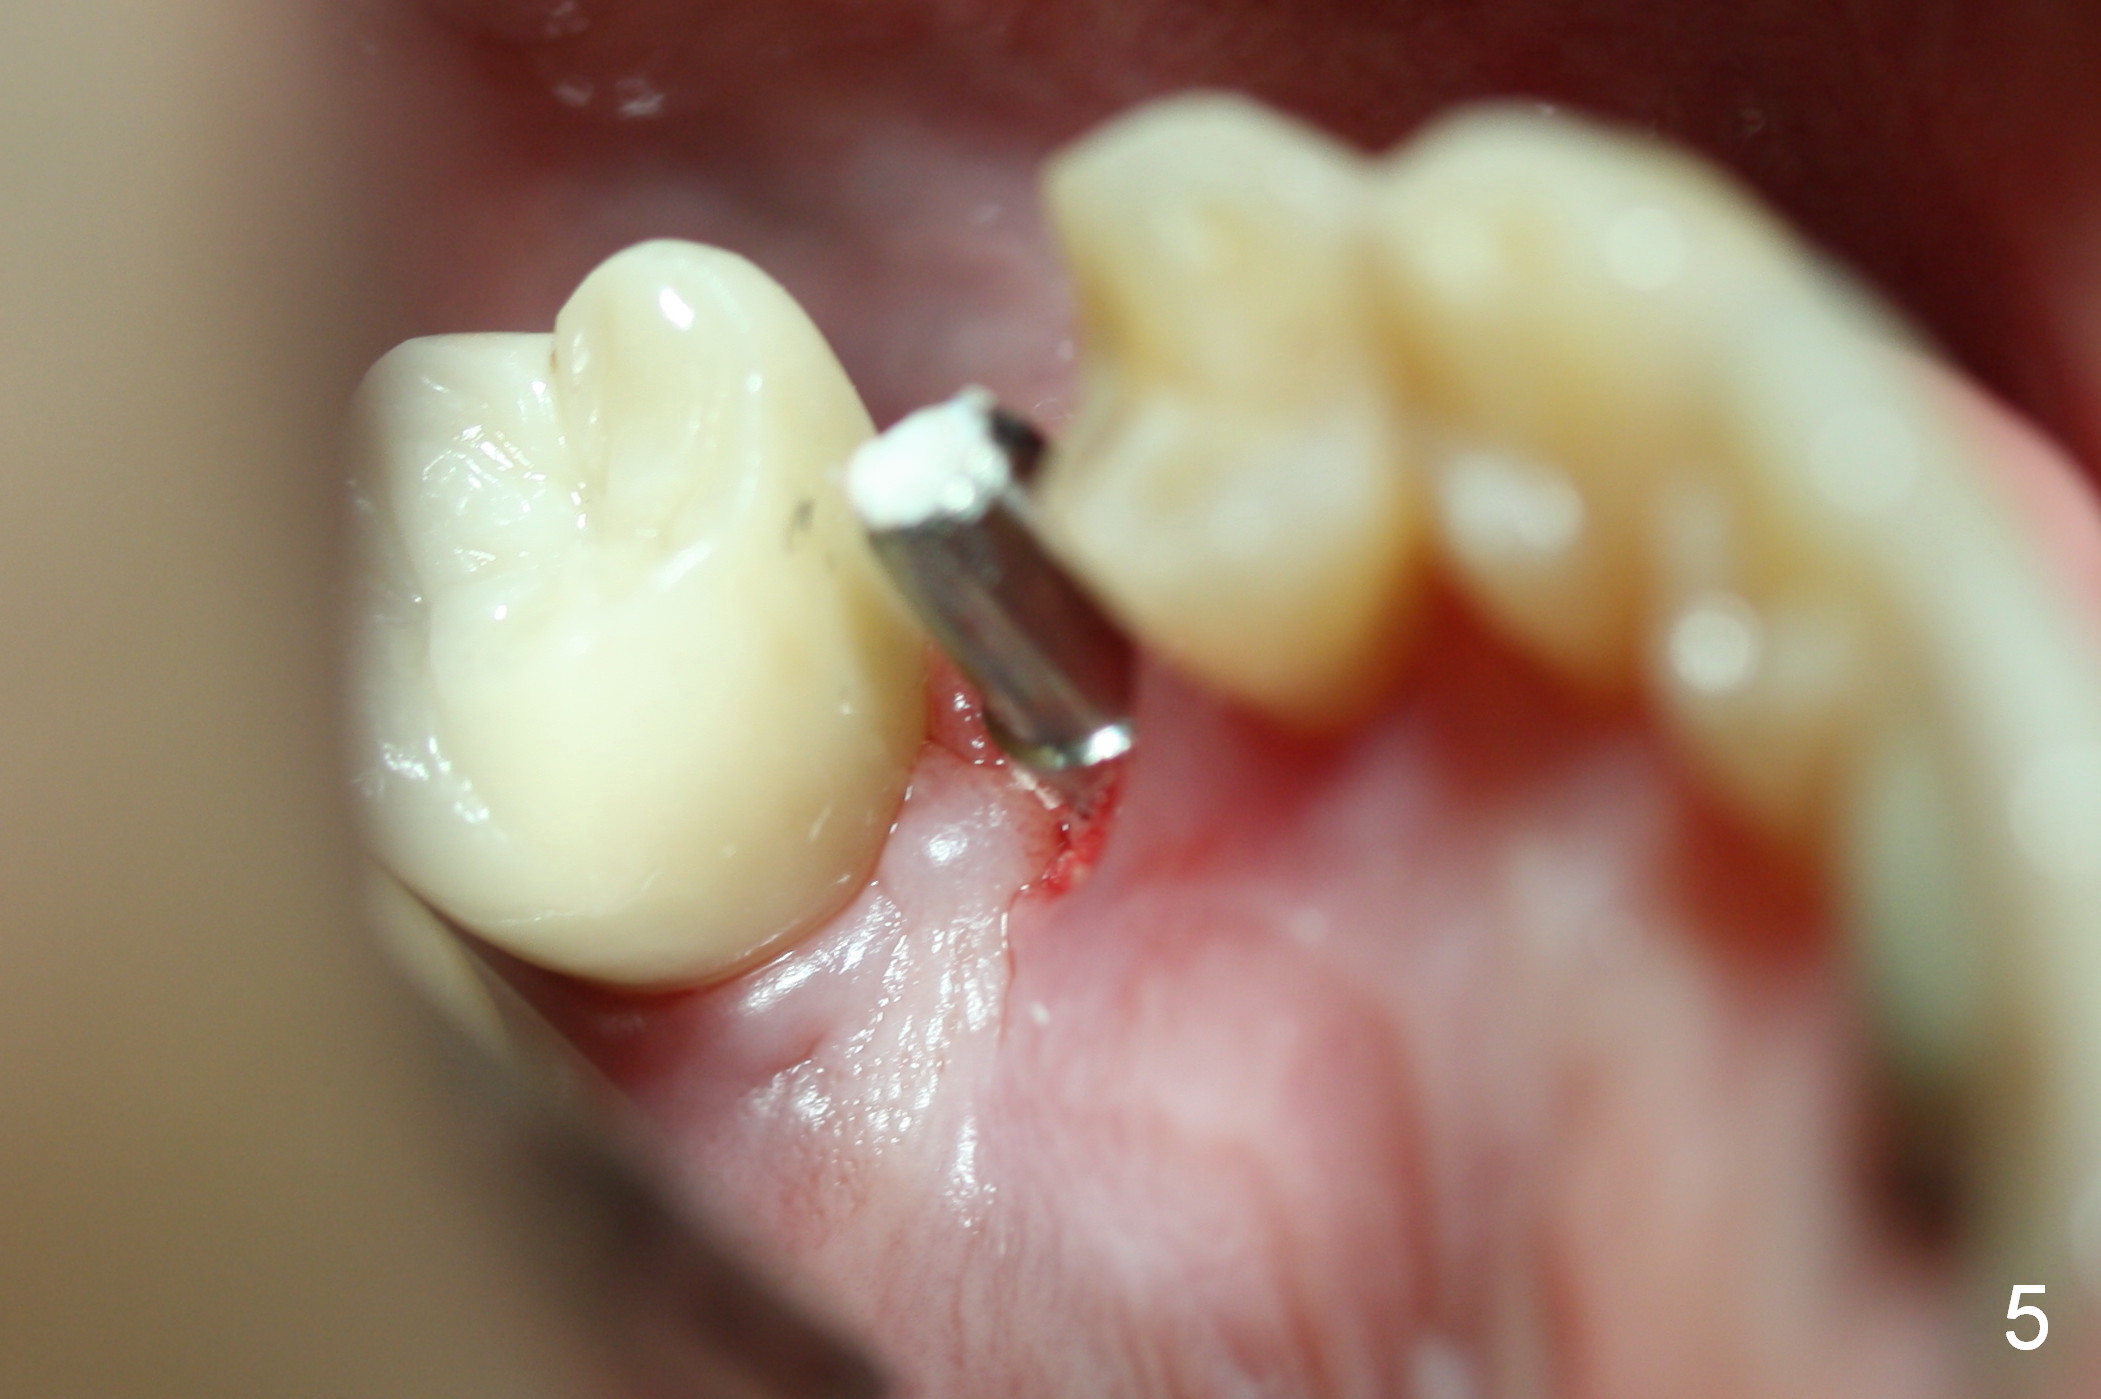

The distal buccal (Fig.1) and palatal (Fig.2) papillae (*) are recessive at the tooth #4.  Following extraction and use of 3.8 mm Magic Drill, a 4.5x13 mm implant is placed lower than the mesial crest (Fig.3) to reduce the chance of the distal implant thread exposure.  The latter is a measure to decrease peri-implantitis.  A 4.5x5.7(4) mm pair abutment is placed (Fig.4,5).  The remaining socket is filled with allograft/Osteogen placement.  The large space between #3 and 4 implants is occupied by the healthy gingiva, where bone graft cannot get in.